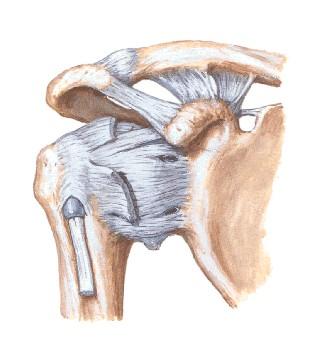

Manguito Rotatorio

Sindrome de pinzamiento Subacromial Síndrome del roce o impigement: irritación mecánica del manguito de los tendones rotadores del hombro por uno o más de los diferentes componentes del arco acromial : acromion, articulación acromioclavicular, ligamento acromiocoracoideo y apófisis coracoides. • NEER DESCRIBIÓ TRES ESTADÍOS. ANAT/PATOLOG • ESTADÍO 1 : EDEMA E INFLAMACIÓN TENDINOSA. • ESTADÍO2 : FIBROSIS Y ENGROSAMIENTO. • ESTADÍO 3 : REACCIÓN ÓSEA Y ROTURA TENDINOSA, PUDIENDO LLEGAR HASTA LA ARTROPATÍA DE LA ROTURA DEL MANGUITO.

: Causas Vasculares: El tendón supraespinoso se ha demostrado, mediante el empleo de Doppler laser, una zona crítica situada a 1cm de su inserción en el troquiter, cuya vascularización es precaria. Causas degenerativas: Las alteraciones degenerativas del manguito rotador, hallazgo fisiológico a partir de la quinta década de la vida. se puede ver agravada por fricción o roce contra la superficie subacromial. Causas mecanicas y traumaticas: Tercio inferior del acromion y el manguito rotador.

CLINICA DE MANGUITO ROTADOR.. • DOLOR ESPECIALMENTE NOCTURNO • SIGNOS DE ROCE Y UN ARCO DE MOVIMIENTO DE SEPARACIÓN DOLOROSO ENTRE 60 Y 120 GRADOS. • RIGIDEZ ARTICULAR. • ATROFIA MUSCULAR. • PÉRDIDA DE FUERZA PARA LA ELEVACIÓN Y LA ROTACIÓN EXTERNA Y CRUJIDOS O CREPITACIÓN EN LA ZONA SUBACROMIAL.